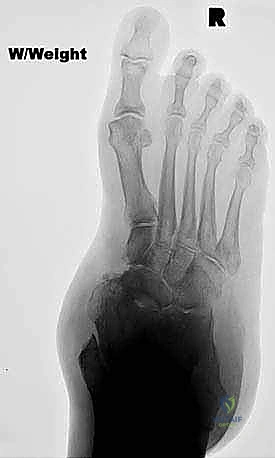

FIG 3 • Radiographs of a 56-year-old diabetic woman with severe pes planovalgus deformity and gross subluxation of the subtalar and transverse tarsal joints radiographically.

Standard weight-bearing radiographs of both the foot and ankle are critical in evaluating severe pes planovalgus deformities. The foot films will determine the amount of subluxation or dislocation of the subtalar and transverse tarsal joints that must be corrected. They can also determine whether there is deformity or bone loss that demands the addition of structural bone grafts. The ankle radiographs are required to confirm that the severe heel valgus is isolated to the hindfoot. Occasionally, severe valgus hindfoot deformity leads to increasing deltoid ligament incompetence, creating a valgus tilt of the talus within the ankle mortise. Deltoid ligament incompetence and valgus tilt of the ankle may necessitate surgical correction of the ankle as well should hindfoot realignment with triple arthrodesis fail to rebalance the tibiotalar joint ( FIG 3 ).

FIG 4 • After single-medial-incision triple arthrodesis, the patient shown in Figure 3 had excellent correction of her deformity without wound-healing complications.